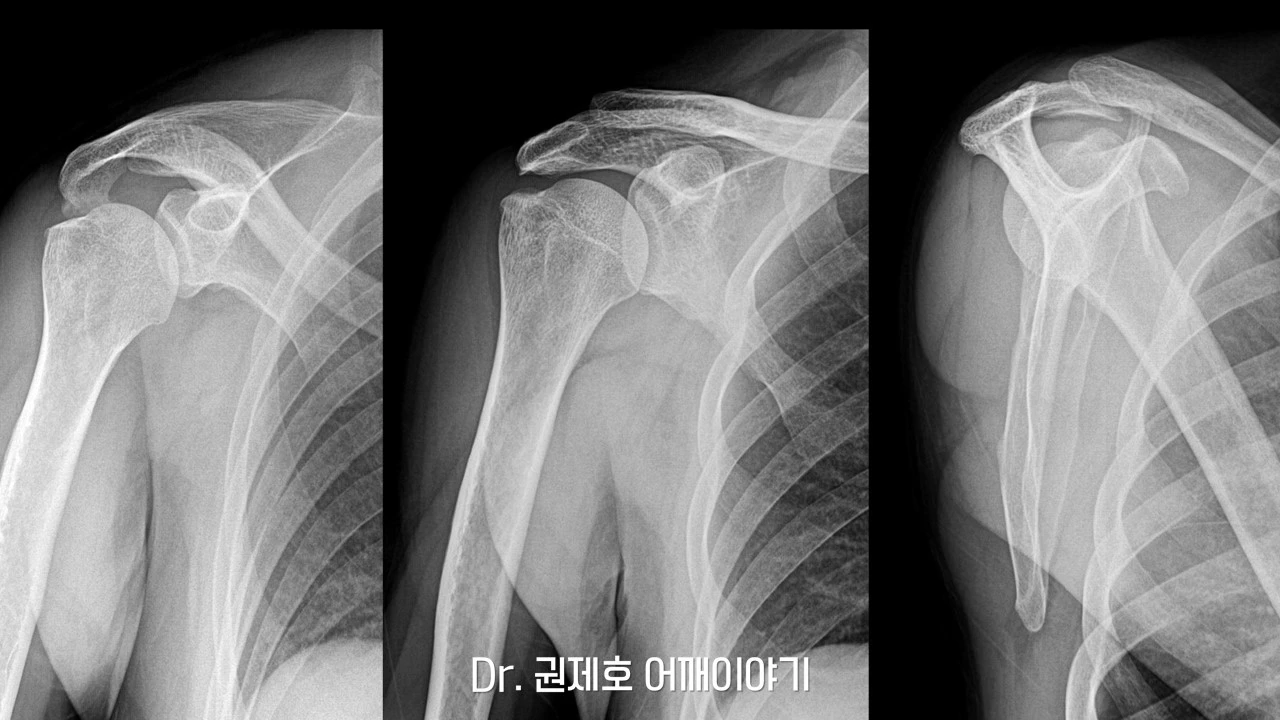

처음에 진료를 보시러 오시면, 기본적인 검사를 하고 진료를 보게 된다. 그 기본적인 검사는 바로 어깨 방사선 촬영이다. 사진에서 보면 '견봉'이라는 뼈 밑으로 오랜 세월에 걸쳐 생긴 '골극'이 관찰된다. 골극이라는 것은 뼈가 자라나는 현상을 나타낸다.